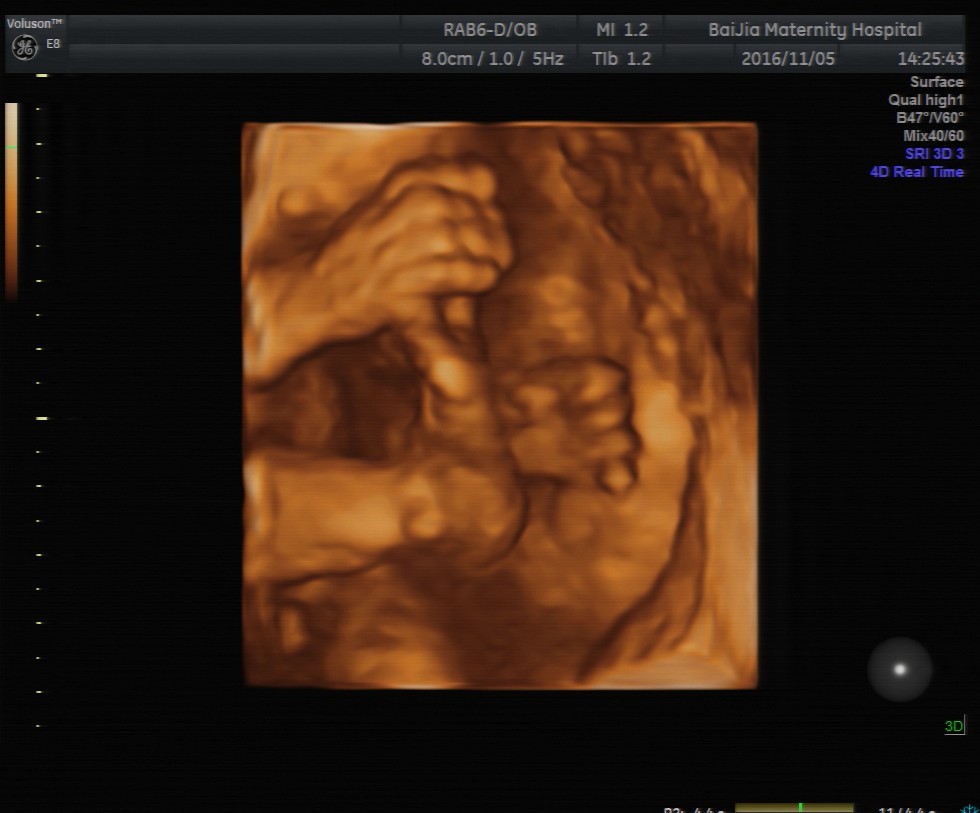

四维彩超能直接观察到胎宝宝发育及在宫内的活动情况,这让很多孕妈咪都很期待做四维彩超检查,但清晰的四维成像对孕周有着严格的要求, 那么, 上海做四维彩超的最佳时间是多

四维彩超能直接观察到胎宝宝发育及在宫内的活动情况,这让很多孕妈咪都很期待做四维彩超检查,但清晰的四维成像对孕周有着严格的要求, 那么,上海做四维彩超的最佳时间是多少周呢?

理论上来讲,孕20—24周是做四维彩超的最佳时间,这个时期是胎儿的快速发育时期,胎儿的基本结构已经形成。同时,适中的胎儿大小及羊水量,给胎儿提供了较大的活动空间,有利于全方位观察胎儿的活动状态。

除了观察胎儿的活动情况,孕中期对胎儿做四维彩超的主要目的是筛查胎儿结构畸形。